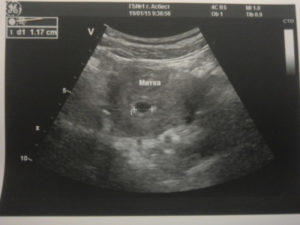

На УЗ-снимке: в полости матки определяются 2 плодных яйца с живыми эмбрионами

На фото: УЗИ плода в начале и в конце 6 недели беременности. На первом изображении определяется плодное яйцо без признаков эмбриона, а на втором, выполненном в конце 6 недели, эмбрион уже виден

На УЗ-снимке: эмбрион на 6 неделе гестации. 1– контур тела матки, 2 – плодный пузырь (хориональная оболочка), 3 – желтое тело, 4 – эмбрион (отчетливо видна начальная стадия дифференциации амниотической оболочки)